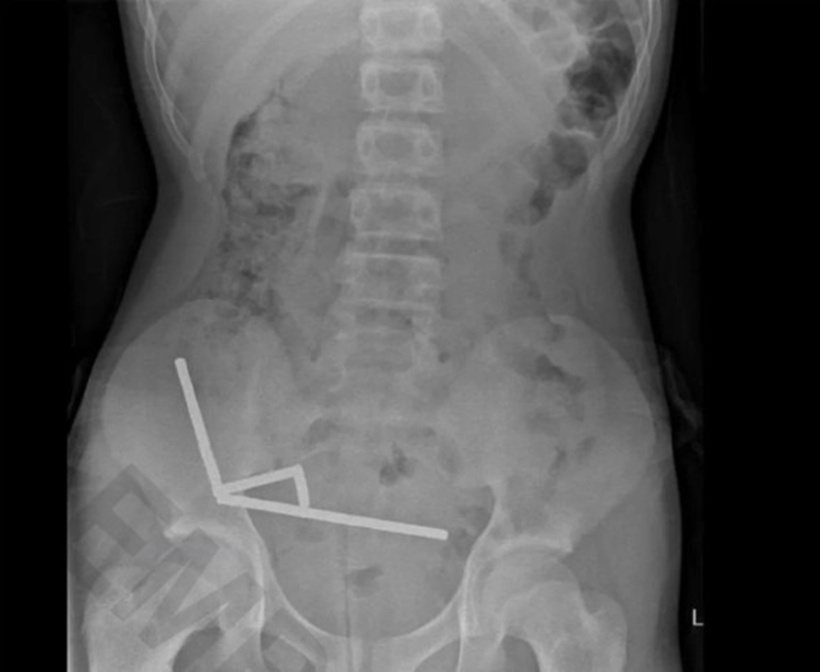

Hình ảnh chụp X-quang cho thấy các viên nam châm đã kết lại thành 4 chuỗi thẳng hàng, mắc kẹt và hút dính vào các phần ruột khác nhau. Lực hút này gây hiện tượng hoại tử tại 4 khu vực của ruột non và manh tràng. Các bác sĩ phẫu thuật đã phải cắt bỏ phần mô bị hoại tử và lấy các viên nam châm ra. Cậu bé đã được xuất viện sau 8 ngày điều trị.

Hình ảnh chụp X-quang cho thấy các viên nam châm đã kết lại thành 4 chuỗi thẳng hàng, Ảnh: New Zealand Medical Journal.